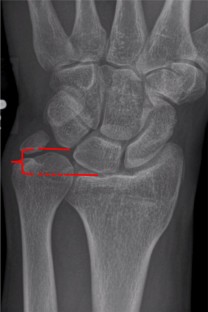

Fig. 8

Fig. 9

Fig. 10